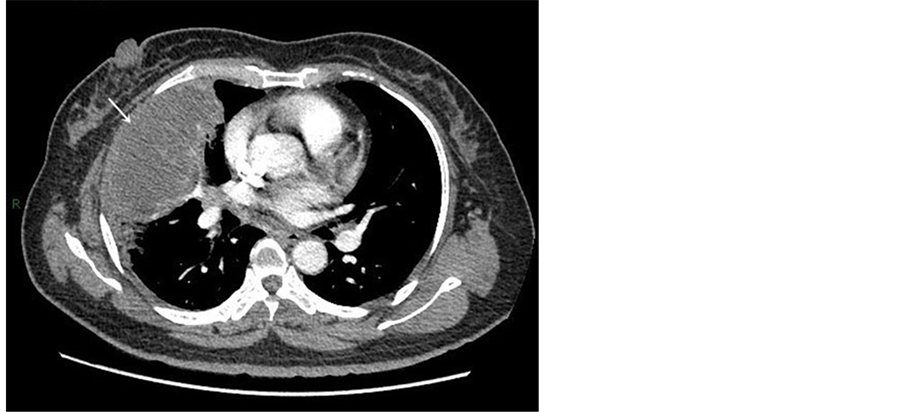

Gynecological examination appeared no obvious abnormity in uterus and adnexa. Transvaginal ultrasonography revealed that the endometrium was 5 mm thick with echo heterogeneity. A well-defined mass with higher density, measuring 8.0 × 5.8 cm, in the right middle lobe of lung was detected on chest X-ray and lobulation and apparent thorn were not found. Chest enhanced computed tomography scan (Figure 1) confirmed the mass and showed a 12.0 cm × 6.5 cm × 8.0 cm space occupying lesion, which corresponded to lung metastasis. It is more likely that the tumor thrombosis located in the confluent locus of veins of right middle lobe lung, superior pulmonary vein and left atrium. Obstructive pneumonia was detected in right middle lobe. Abdominal CT showed

Figure 1. Computed tomography scan showed a massive mass in the right lung (white arrow), measuring 12.0 cm × 6.5 cm × 8.0 cm.